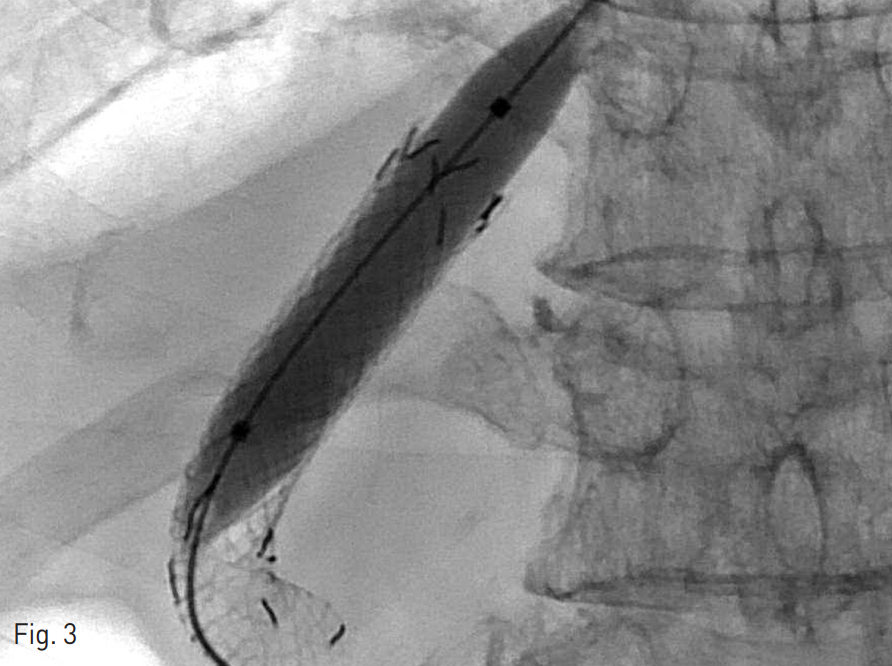

Fig. 3

10mm balloon was expanded to untie the suture of the previously revised stent graft.

시술 이후에도 3등급의 간성혼수 증상이 지속되어 2주 뒤 다시 두 번째 revision을 계획하였다. 시술 전 문맥-간정맥 압력 차는 11 mmHg였다. 10 mm x 6 cm 풍선 카테터 (Mustang, Boston Scientific, Natick, MA, USA)를 이용하여 첫 번째 revision때 삽입하였던 stent의 6mm로 좁혔던 부분을 펴준 뒤 (Fig. 3) 두 군데를 5 mm로 묶어서 만든 10 mm stent graft를 내부에 재설치하였다 (Fig. 4). 시술 이후 문맥간정맥압 차이는 16 mmHg로 측정되었다. 이후 환자의 간성혼수 증상이 grade 2로 호전되었다.